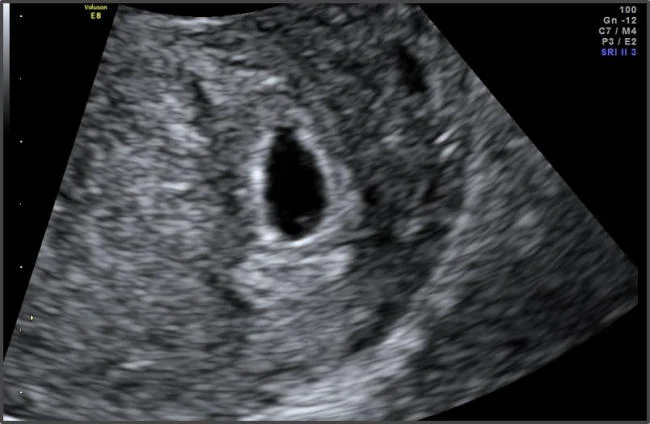

Túi thai là gì?

Túi thai (gestational sac) là cấu trúc đầu tiên của thai kỳ có thể quan sát được trên siêu âm. Nó là một túi nhỏ chứa dịch nằm trong tử cung và bao bọc phôi thai đang phát triển.

Thai mấy tuần thì có túi thai trên siêu âm?

Thời điểm thấy túi thai phụ thuộc vào loại siêu âm và nồng độ hCG trong máu.

Theo các tài liệu y khoa, khi nồng độ hCG đạt khoảng 1500–2000 mIU/mL, túi thai thường có thể nhìn thấy trên siêu âm đầu dò.

Bước 3: Siêu âm đầu dò

Siêu âm đầu dò giúp:

- phát hiện túi thai sớm hơn

- nhìn rõ cấu trúc thai